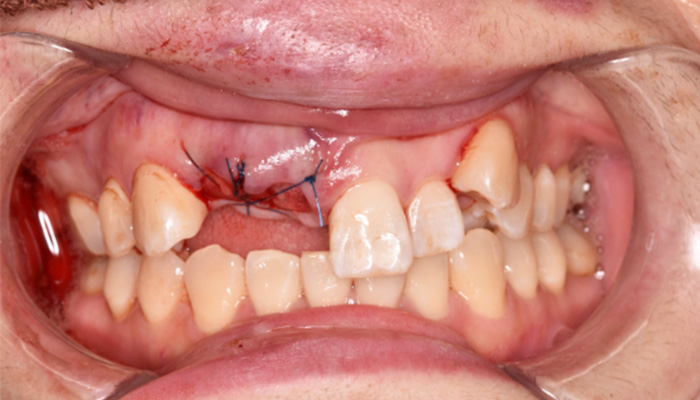

【40代女性】前歯のインプラント症例

「根が折れてしまった歯を

インプラントにしたい」

治療前

治療中

治療後

津田先生からのコメント

前歯のインプラントで特に審美的に要求の高い患者様でしたので、当院で最も信頼性の高いインプラント治療プランをご選択いただきました。また、前歯の左右差をコンポジットレジン(CR)修復治療で整えました。

| 主訴 | 根が折れてしまった歯をインプラントにしたい。 合わせて前歯の左右差を治したい。 |

|---|---|

| 治療期間 | 約4ヶ月 |

| 治療費 | 1本あたり550,000円(税別) |

| 治療内容 | 前歯のインプラント治療 |

| 治療のリスク | 前歯のインプラント治療では、審美性の問題や骨密度不足によるインプラントの不安定、神経損傷や感染のリスクがあり、術後の腫れや痛みも発生する可能性があります。 |